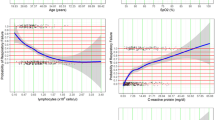

The AUROC of the model was 0.920 (95% CI 0.902–0.938), indicating a greater capability to discriminate NCP than WBC count (AUROC 0.727, 95% CI 0.692–0.762) or chest imaging score (AUROC 0.795, 95% CI 0.766–0.825) (Fig. 1). To internally examine whether the model was over fitted, we used fivefold Cross-Validation of the trained model, and repeated the cross-validation for 10 times. It showed that the mean of AUROC was of 0.916 with the standard deviation of 0.017. The Hosmer–Lemeshow test which measured the calibration showed a χ2 of 10.857 (P = 0.210), demonstrating that there was no significant difference from a perfect fit. The patients with NCP had a model score of 3.60 ± 2.41, higher than those without NCP (model score = −0.42 ± 1.69, P < 0.001) (Fig. 2). At a cut-off value of 1.0, the rapid screening model could determine NCP with a sensitivity of 85% (95% CI 81.2–88.8%), a specificity of 82.3% (95% CI 80.6–84.0%), a diagnostic accuracy of 83.2% (95% CI 80.7–85.7%), and a Youden index of 0.673.

Receiver-operating characteristic (ROC) curves of the predictive model 1 and its included features for detecting novel coronavirus pneumonia. The area under the ROC curve was 0.920 (95% CI 0.902–0.938), 0.727 (95% CI 0.692–0.762), 0.795 (95% CI 0.766–0.825), with a standard error of 0.009, 0.018, and 0.015 for predictive model 1, WBC count, and chest imaging score. The optimized Youden based cutoff was 1.00, 6.20, and 0.15, respectively. The sensitivity and (1-specificity) of the binary factors were also illustrated. WBC: white blood cell.